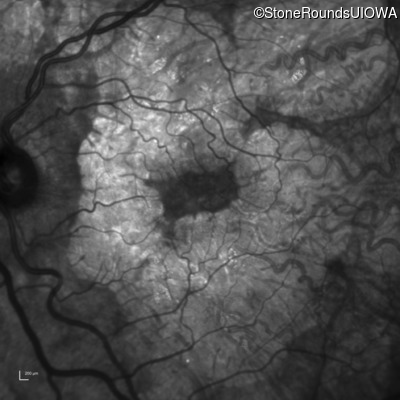

AR Stargardt Disease (IIA)

Age at visit: 51 years

This 51 year old woman first experienced some abnormality in her distance vision when she was 27 years old. She feels that her vision has been stable since that time.

Diagnosis & molecular findings

Disease Gene Allele 1 variant(s) Allele 2 variant(s) Inheritance mode

AR Stargardt Disease ABCA4 Gly1507Arg GGG>AGG IVS42+1 G>A AR